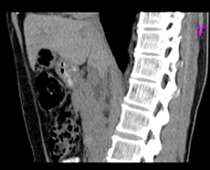

患者,男,57,常年不吃午饭,近一个月来腹部隐痛,无明显黄疸,明天进行增强扫描,图象另上传,麻烦各位帮忙一起看看讨论讨论

肝外胆管扩张,胰头增大,肠系膜上静脉似有包埋征象。

考虑:胰头占位性病变,建议增强进一步检查。

肝外胆管扩张,胰头增大,占位性病变可能性大.

肝内外胆管扩张,胆管未端阻塞,建议mri检查

肝外胆管稍扩张,胰腺钩突略增大,但外形尚可,境界清楚。(常年不吃午饭)提示胰腺炎可能大,肿瘤第二步考虑。

胰头增大,胆总管增宽,考虑胰头癌可能性大,明天看增强片有助诊断.